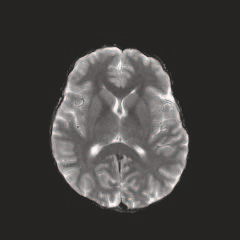

Multi-modal medical image completion has been extensively applied to alleviate the missing modality issue in a wealth of multi-modal diagnostic tasks. However, for most existing synthesis methods, their inferences of missing modalities can collapse into a deterministic mapping from the available ones, ignoring the uncertainties inherent in the cross-modal relationships. Here, we propose the Unified Multi-Modal Conditional Score-based Generative Model (UMM-CSGM) to take advantage of Score-based Generative Model (SGM) in modeling and stochastically sampling a target probability distribution, and further extend SGM to cross-modal conditional synthesis for various missing-modality configurations in a unified framework. Specifically, UMM-CSGM employs a novel multi-in multi-out Conditional Score Network (mm-CSN) to learn a comprehensive set of cross-modal conditional distributions via conditional diffusion and reverse generation in the complete modality space. In this way, the generation process can be accurately conditioned by all available information, and can fit all possible configurations of missing modalities in a single network. Experiments on BraTS19 dataset show that the UMM-CSGM can more reliably synthesize the heterogeneous enhancement and irregular area in tumor-induced lesions for any missing modalities.